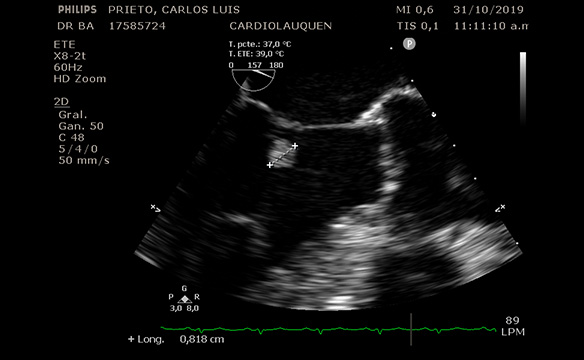

Paciente de 56 años de edad, sin antecedentes patológicos que consulta en nuestro centro a la Dra. Barr por episodio sincopal mientras se encontraba en baile.

TA : 120-80 mm hg. No soplos. Pulsos y pulmones normales. ECG normal. Afebril.

ECO DOPPLER y ETE, equipo Phillips 3D (Dra. Barr y Tec. En imágenes Lucia Vacas): imagen en Valva Mitral redondeada de 0.8 mm, muy móvil, sin compromiso de ecoestructura Mitral luego fue evaluado en consulta con Dr. Avegliano, confirmando la sospecha de que por las características de dicha masa puede corresponder a Fibroelastoma Papilifero. Dada la alta incidencia de embolia, se envía a Cirugía Cardiovascular.

Fecha: Nov. 2019

Aparato: Eco Doppler/ETE

Autor: Dra. Barr